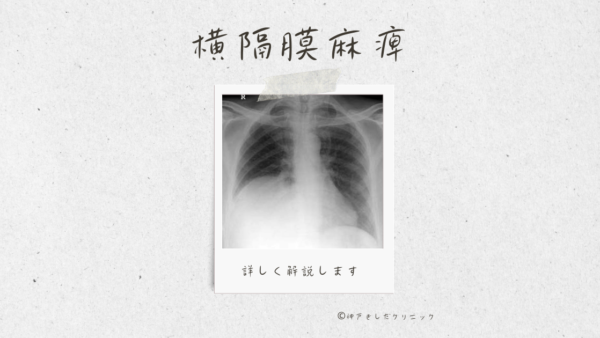

胸部単純X線写真の見方—胸腺陰影を中心に (LiSA 29巻12号) | 医書.jp, 尿崩症 縦隔腫瘍 - Genspark,

尿崩症 縦隔腫瘍 - Genspark, 縦隔腫瘍(じゅうかくしゅよう Mediastinal tumor) – 呼吸器疾患,

縦隔腫瘍(じゅうかくしゅよう Mediastinal tumor) – 呼吸器疾患, 尿崩症 縦隔腫瘍 - Genspark,

尿崩症 縦隔腫瘍 - Genspark, 頸胸部 CT の術後経過 : a )術前, b )術後 1 日目, c )術後22日,

頸胸部 CT の術後経過 : a )術前, b )術後 1 日目, c )術後22日, 胸部X線の正常・異常画像を見極める〜日常診療で出合う境界症例,

胸部X線の正常・異常画像を見極める〜日常診療で出合う境界症例, 112F47 | 医原性・化学物質による肺障害 国試 | テコプラ,

112F47 | 医原性・化学物質による肺障害 国試 | テコプラ, 一般撮影|大阪母子医療センター,

一般撮影|大阪母子医療センター, 胸腺腫(きょうせんしゅ Thymoma) – 呼吸器疾患 - 神戸きしだ,

胸腺腫(きょうせんしゅ Thymoma) – 呼吸器疾患 - 神戸きしだ, 一般撮影|大阪母子医療センター,